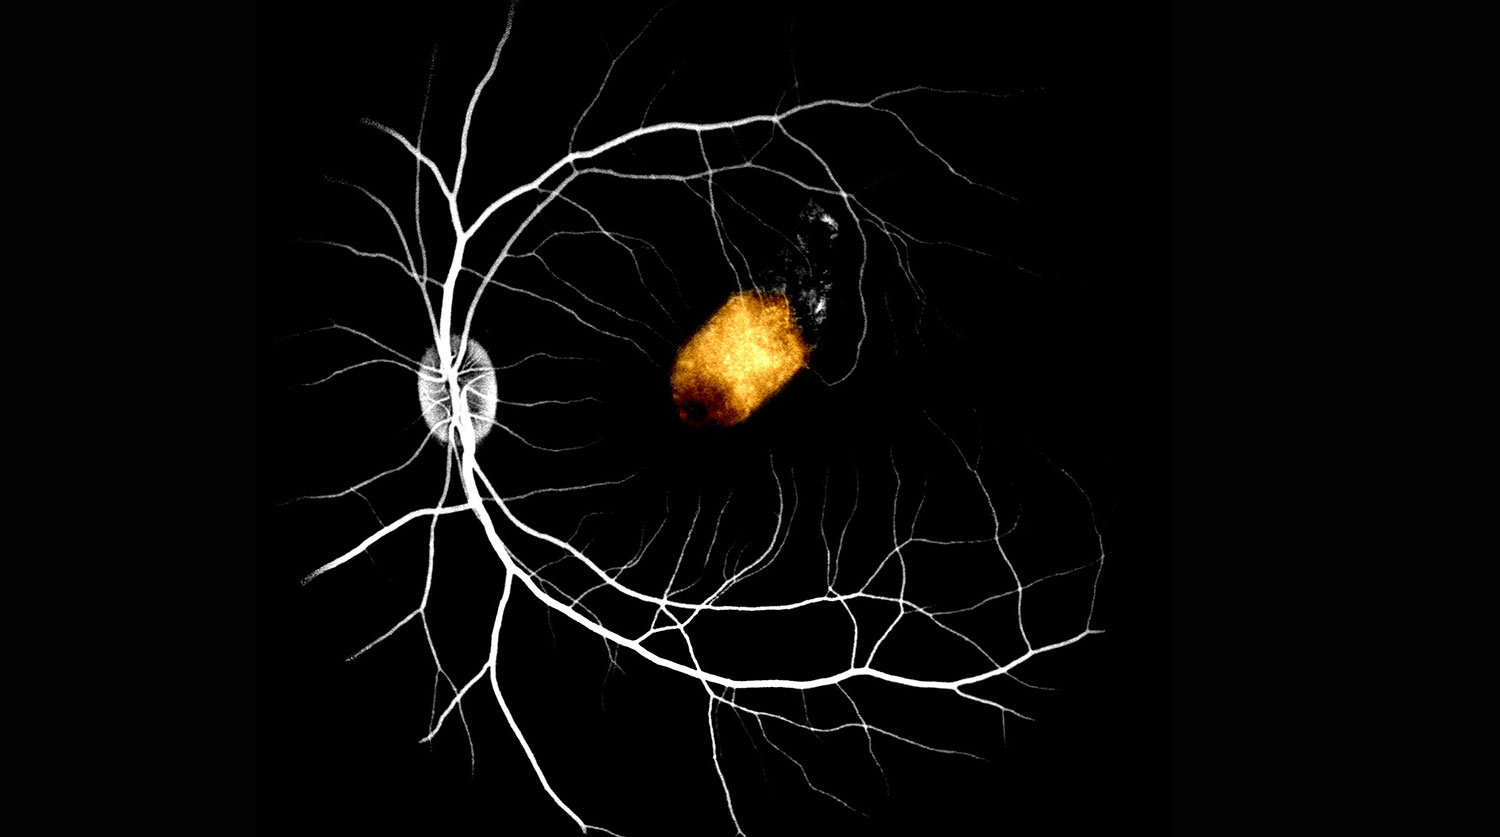

Пигментный эпителий сечтатки из стволовых клеток глаза человека, пересаженный на сетчатку макаки

Исследователи использовали стволовые клетки сетчатки, полученные от двух умерших пожилых людей. Они пересадили их на желтое пятно — место наибольшей остроты зрения в сетчатке — девяти макак. Эксперимент проводился пока что на здоровых животных, чтобы понять, возможна ли вообще подобная пересадка. Клетки успешно прижились, на протяжении трех месяцев не наблюдалось никаких серьезных побочных эффектов.

Более того, пересаженные клетки оказались способны взять на себя функции пигментного эпителия сетчатки обезьян, что дает потенциальную возможность в будущем использовать такой метод для борьбы со слепотой.

«Мы продемонстрировали, что пигментный эпителий сетчатки, полученный от человеческих трупов, способен по крайней мере частично взять на себя функцию желтого пятна у приматов, — говорит автор статьи и клеточный биолог Тимоти Бленкинсоп. — Клетки, полученные от мертвого донора, можно безопасно трансплантировать под сетчатку и компенсировать ее функцию у хозяина, поэтому их применение для борьбы с потерей зрения у пациентов с заболеваниями сетчатки выглядит очень многообещающе».